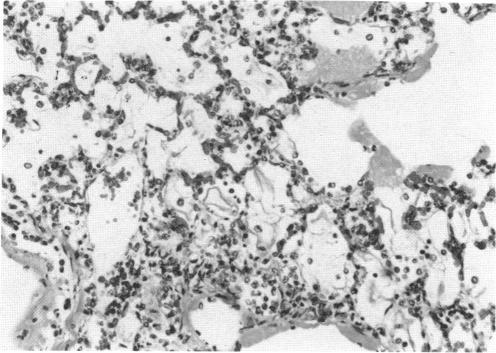

The morphologic changes induced in the lungs of rats and guinea pigs exposed to high concentrations of MIC vapor (100, 600, and 1000 ppm in the rat and 25, 125, 225, and 675 ppm in the guinea pig) for a short time (15 min) in a static exposure chamber were evaluated at varying postexposure periods (0, 1, 2, 4, and 16 hr). The 675 ppm-exposed guinea pigs were evaluated only immediately following removal from the chamber. Attention was primarily focused on the intrapulmonary conducting airways and the parenchyma (gas exchange region) of the lungs. The severity of morphologic changes observed by light microscopy was directly correlated with exposure concentration and time postexposure in both species. Specifically, degenerative changes were observed in the bronchial, bronchiolar, and alveolar epithelium in both species. Quantitative differences were observed; 100 ppm of MIC in the rat resulted in much less damage than did 125 ppm of MIC in the guinea pig. Morphologic evidence of sloughing of large sheets of conducting airway epithelium with fibrin buildup and increased mucus production resulted in plugging of major airways and atelectasis. These observations support the hypothesis that tissue hypoxia was a major contributing factor resulting in death.